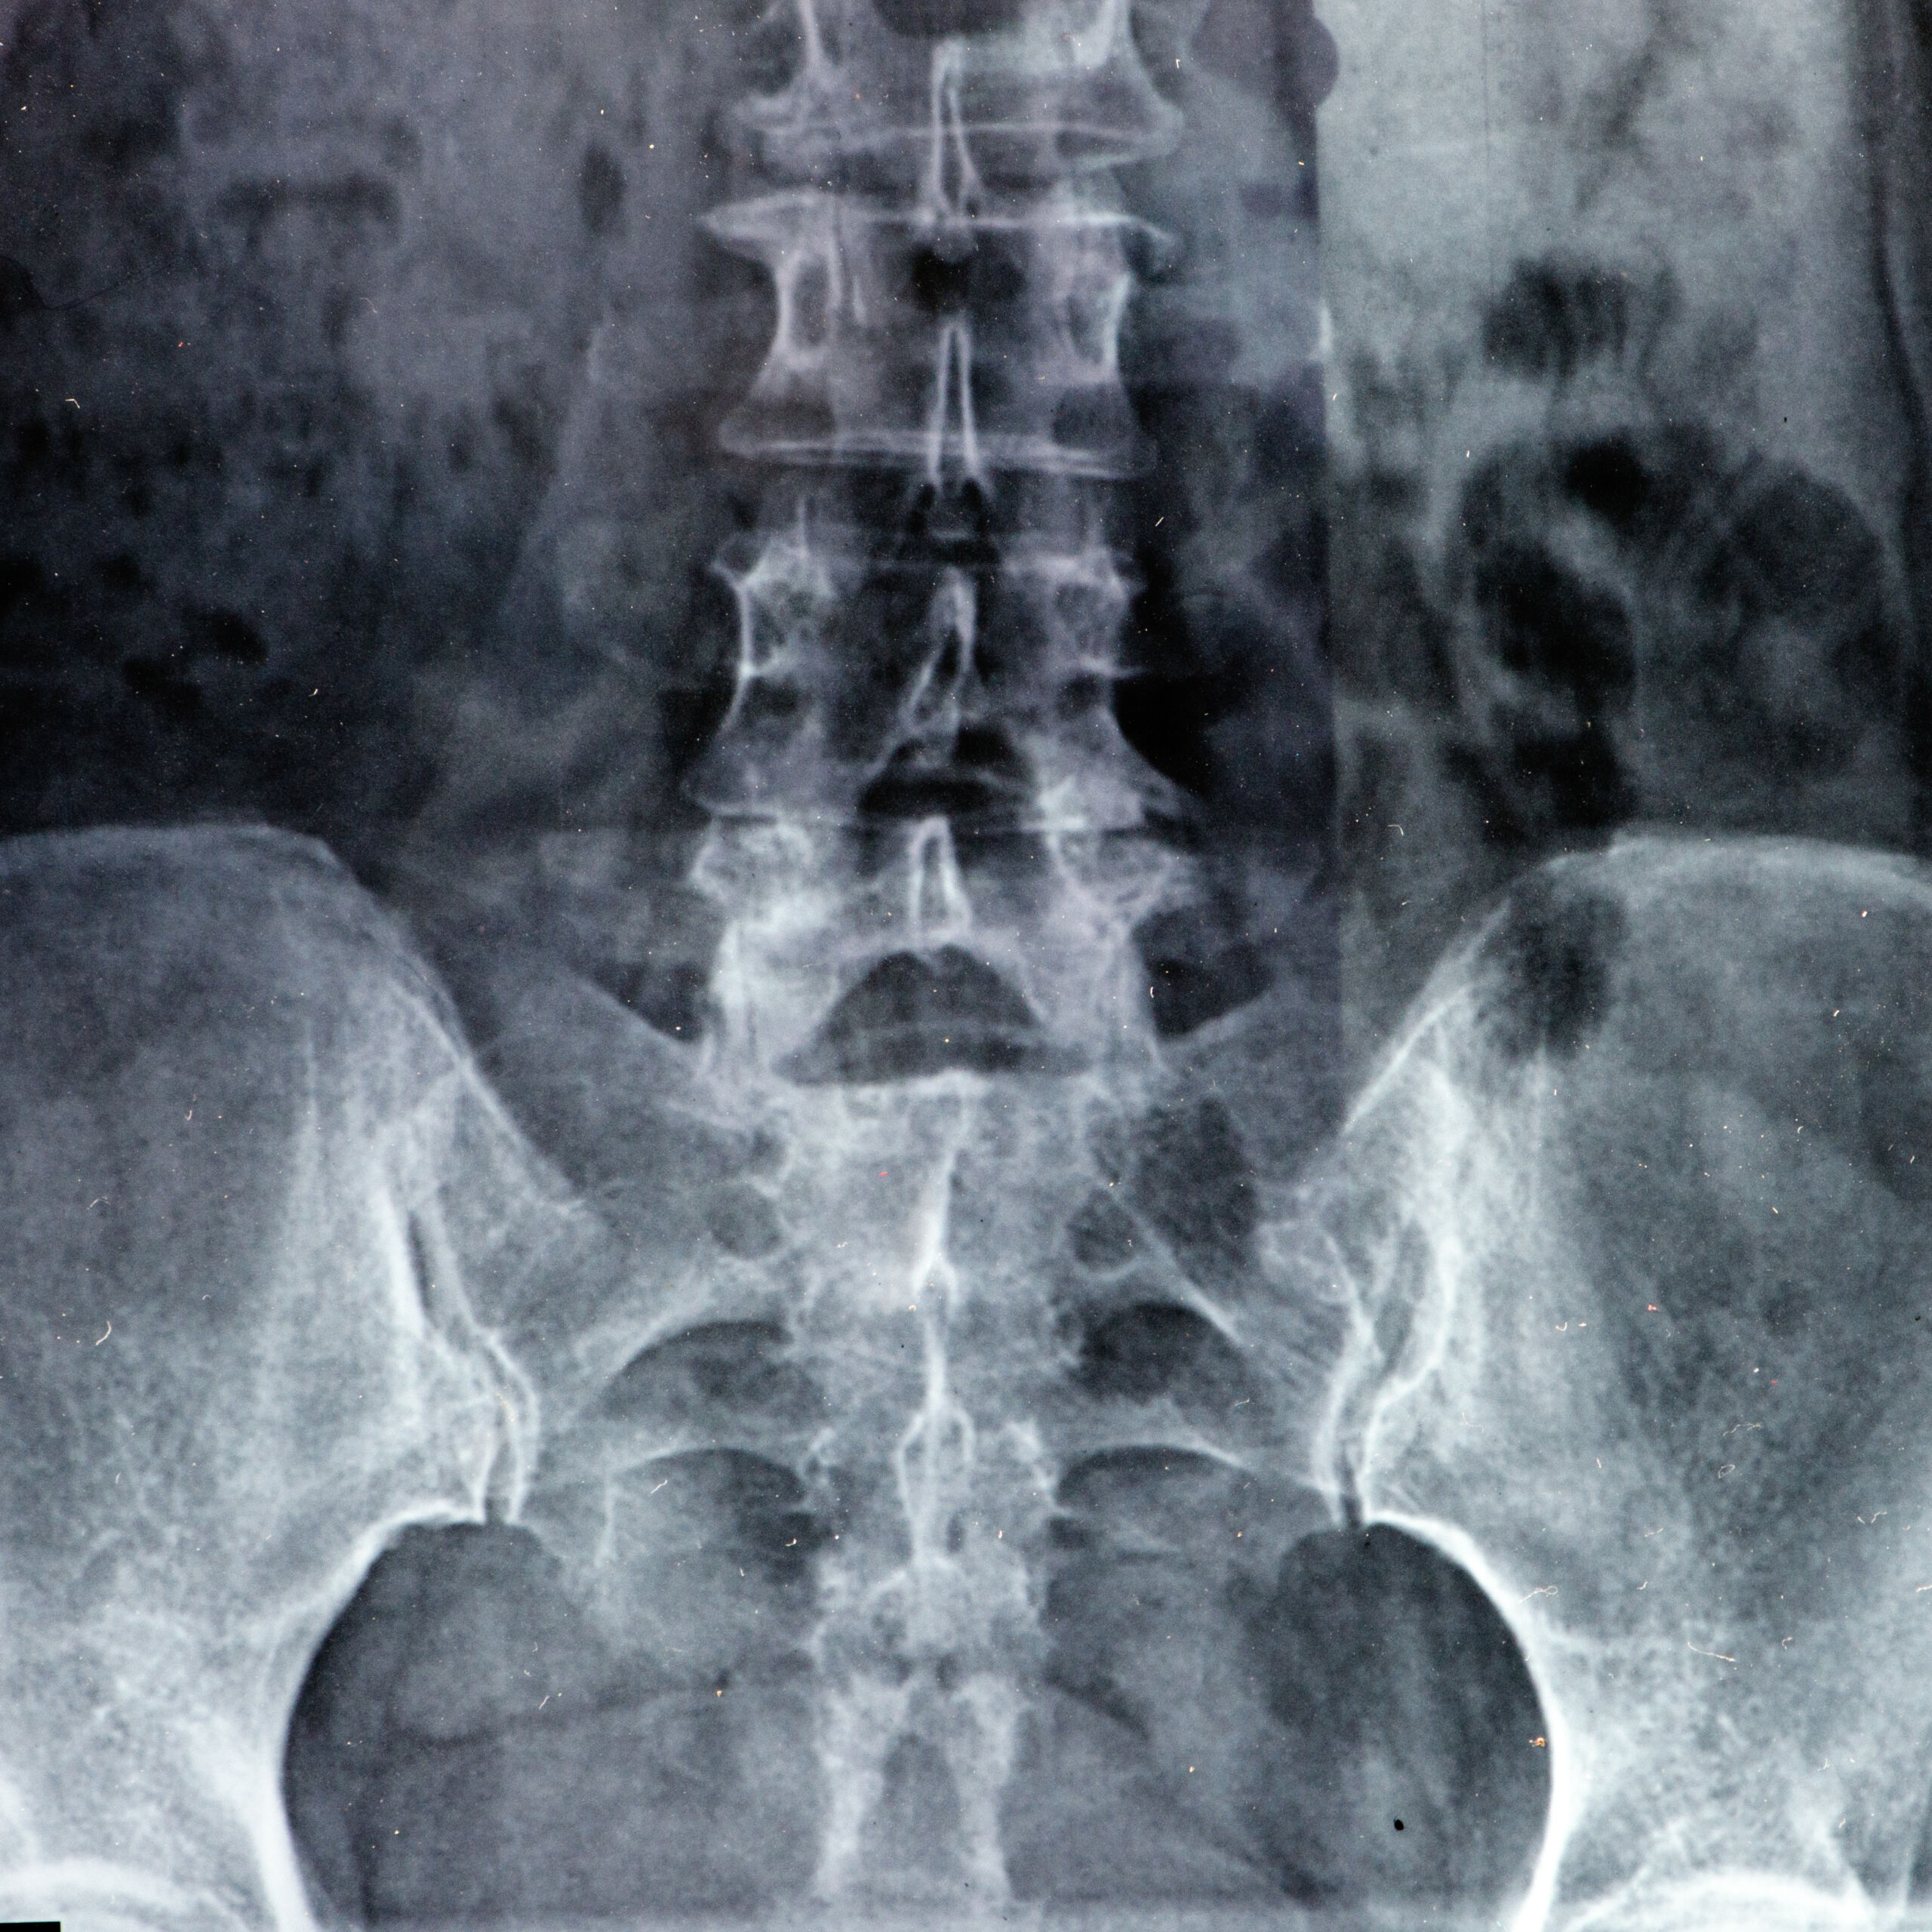

Cauda equina syndrome (CES) is a rare but serious neurological condition where the bundle of nerve roots at the lower end of the spinal cord (the cauda equina) becomes compressed. This compression can cause permanent paralysis, loss of bowel and bladder control, sexual dysfunction and chronic pain if not diagnosed and treated extremely quickly — usually within 24–48 hours of symptom onset.

Medical negligence in cauda equina syndrome cases most commonly occurs when doctors or hospitals fail to recognise the classic “red flag” symptoms or do not act with the necessary urgency. These red flags include severe low back pain with sciatica in both legs, saddle anaesthesia (numbness in the buttocks, genitals and inner thighs), urinary or bowel dysfunction (incontinence or retention), and sexual dysfunction. When these symptoms are missed, misdiagnosed as simple sciatica or back strain, or when MRI scanning and emergency surgery are delayed, medical negligence often results in irreversible nerve damage.